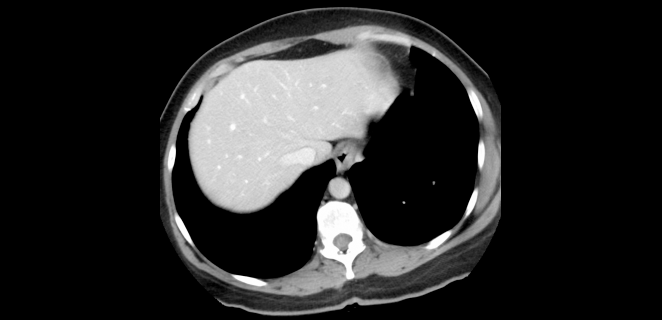

الاشعة المقطعية للكبد

تعرف الأشعة المقطعية CT Scan بأنه طريقة تصوير للجسم تستخدم